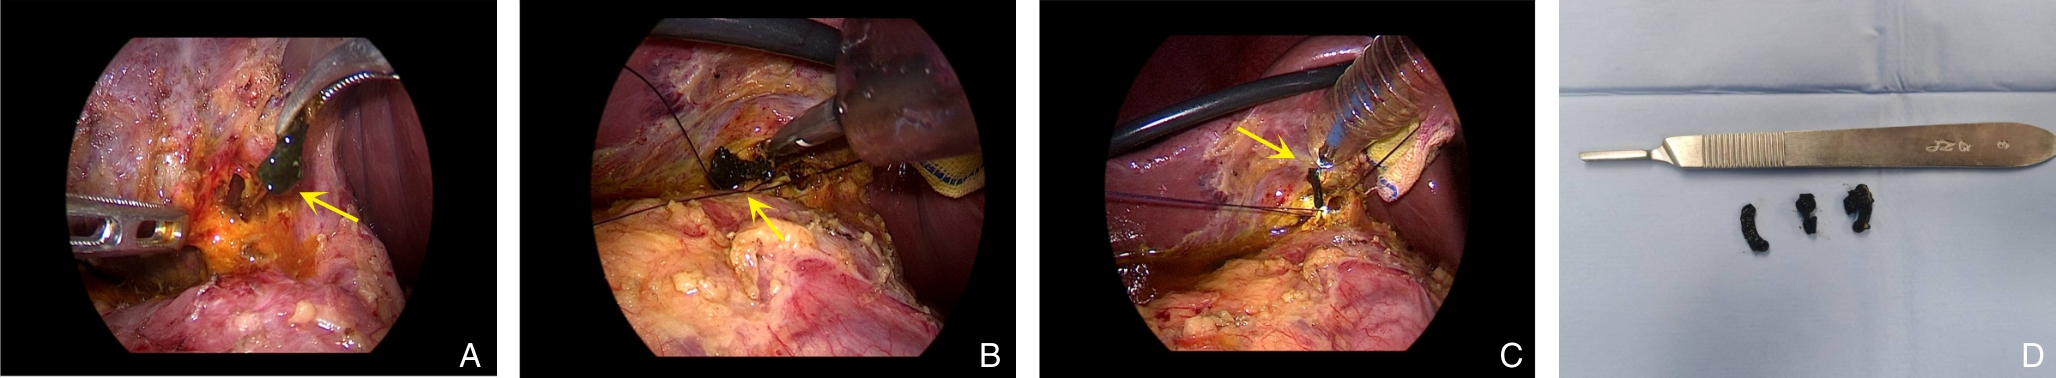

背景与目的 Hem-o-lok夹广泛应用于腹腔镜胆囊切除术(LC)中的胆囊管及血管闭合,但其术后移位虽罕见,却可进入胆总管形成异物,影像学表现易误诊为胆总管结石,增加诊断与治疗难度。针对该远期并发症的识别与处理,临床认知仍有不足。本文通过分析1例相关病例并结合文献复习,总结其临床特征及诊治要点。方法 回顾性分析中国人民解放军空军军医大学第二附属医院普通外科2025年10月收治的1例29岁女性患者的临床资料。患者4年前行LC,本次因体检发现“胆总管结石”1年余入院,术前影像学提示胆总管多发充盈缺损。患者拒绝内镜下逆行胰胆管造影治疗,遂行腹腔镜胆总管探查术(LCBDE),术中确诊为Hem-o-lok夹移位。分析其诊疗过程、影像学特征及术中所见,并结合文献进行讨论。结果 术前影像学提示胆总管多发结石。LCBDE术中经胆道镜探查,于胆总管中下段取出3枚移位的Hem-o-lok夹,周围未见胆色素结石,确诊为“胆总管异物(Hem-o-lok夹)”。术后置T管引流,恢复顺利出院。术后2个月T管窦道造影示胆总管通畅,无残留异物或结石,顺利拔管。结论 Hem-o-lok夹移位是LC术后一种罕见的远期并发症,影像学易误诊为胆总管结石。对有相关手术史的患者,应将其纳入鉴别诊断。LCBDE是确诊及处理该并发症的有效方式。规范术中操作及合理选择闭合方式,并加强术后随访,有助于降低此类并发症风险。

背景与目的 腹腔镜胆总管切开取石术(LCBDE)是胆总管结石的主要微创治疗方式。“单孔+1”腹腔镜技术(SILS+1)在胆囊手术中已显示出微创优势,但其在胆总管切开取石中的安全性与有效性仍有争议。本研究在统一应用吲哚菁绿(ICG)荧光胆管显影及自脱落胆道支架条件下,比较SILS+1与传统多孔LCBDE的围手术期疗效与安全性。方法 回顾性分析2024年3月—2025年3月接受LCBDE治疗的132例胆总管结石患者,根据手术方式分为SILS+1组(n=32)与传统多孔组(n=100)。采用倾向性评分匹配后纳入SILS+1组32例、传统多孔组64例。比较两组术中指标、术后恢复、并发症发生率及美容满意度等。结果 两组手术时间及胆管缝合时间差异无统计学意义(均P>0.05)。SILS+1组标本取出时间更短,切口总长度更小,术后24 h疼痛评分更低,腹壁美容满意度更高(均P<0.001)。两组在术中出血量、住院时间、住院费用及并发症发生率方面差异无统计学意义(均P>0.05)。所有胆汁漏患者经保守治疗恢复,无需再次手术;两组均无残余结石及支架相关并发症。结论 在统一ICG荧光导航及胆道自脱落支架辅助条件下,SILS+1 LCBDE在不增加并发症发生风险的前提下,可进一步减少手术创伤、减轻术后疼痛并改善美容效果,是一种安全、可行的微创手术方式,但其长期疗效仍需进一步研究验证。